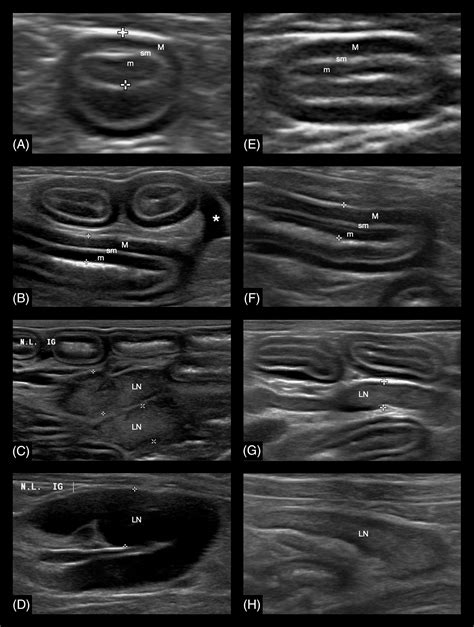

• Imaging studies: X-rays, ultrasounds, and CT scans can help visualize the intestines and detect any abnormalities.

• Endoscopy: An endoscope can be used to examine the intestinal lining and obtain tissue samples for biopsy.

• Biopsy: A biopsy of the affected tissue is often necessary to confirm the diagnosis of intestinal lymphoma.